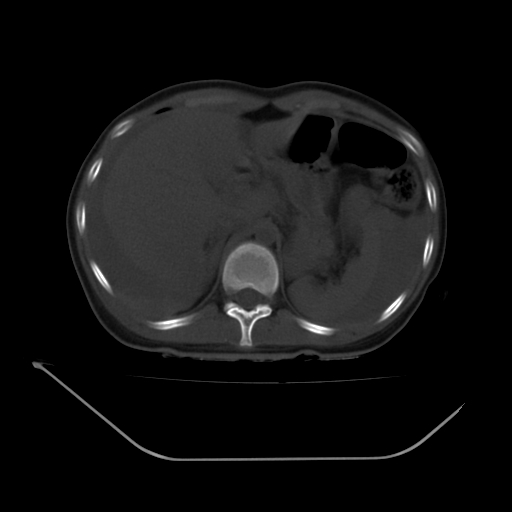

以下是引用liuyue在2008-7-19 13:02:00的发言:[br]1.肝右叶后下段及右肾挫裂伤伴腹腔积血。[br]2.右侧多发性肋骨骨折、横突骨折、右髂骨骨折伴周围软组织挫伤。[br]3.右侧腰大肌肿胀,并可见低密度影,如为气体,则肠道挫裂伤待除外。

以下是引用zhengfaming在2008-7-19 14:42:00的发言:[br]1.肝右叶后下段及右肾挫裂伤伴腹腔积血。脾脏挫裂伤待排[br]2.右侧多发性肋骨骨折、横突骨折、右髂骨骨折伴周围软组织挫伤。[br]3.右侧腰大肌肿胀,并可见低密度影,如为气体,则肠道挫裂伤待除外

以下是引用道哥在2008-7-19 16:52:00的发言:[br]肝右叶后下段及右肾挫裂伤、脾破裂伴腹腔积血。[br]2.双侧多发性肋骨骨折、横突骨折、右髂骨骨折伴周围软组织挫伤。[br]3.右侧腰大肌肿胀,并可见低密度影,如为气体,则肠道挫裂伤待除外。